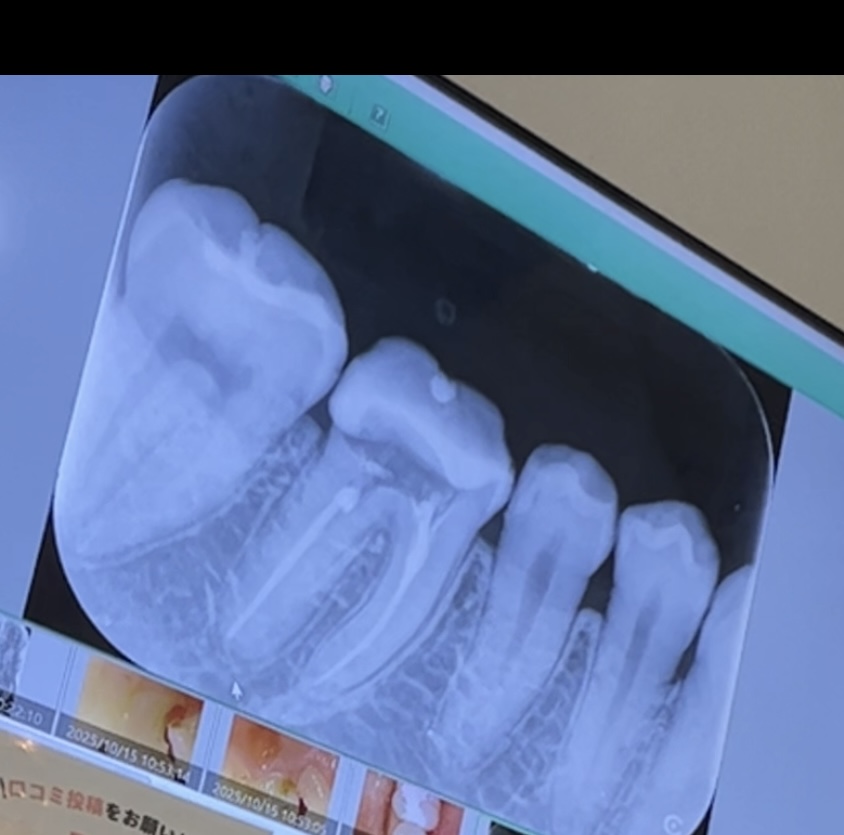

根管治療後、土台を入れた歯がじわじわと痛むようになりました。